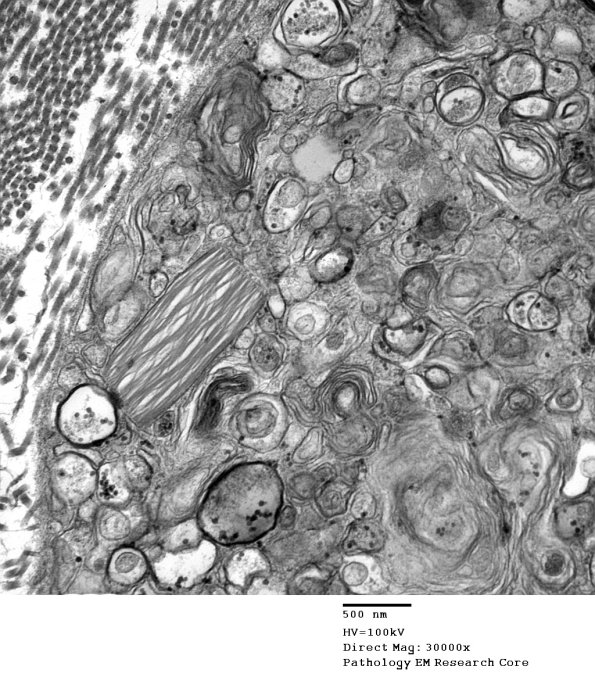

2E4 Axonal Degeneration (Case 7) EM 005 - Copy

A complex admixture of all the myelin, axon and Schwann cell cytoplasm.